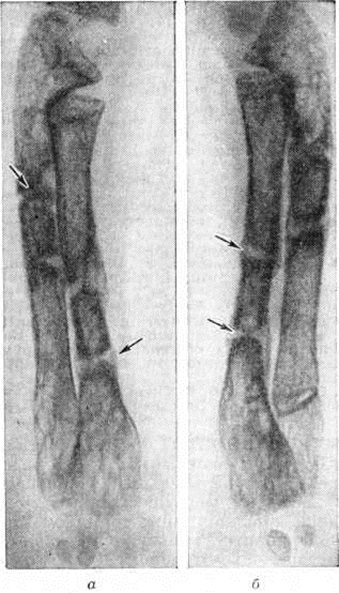

Медицинские аспекты заболеваний: рентгенологическая картина туберкулеза костей

Раздел: Снимки-откровения